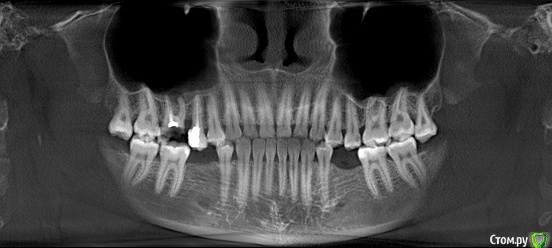

marilinka Опубликовано 4 июня, 2015 Поделиться Опубликовано 4 июня, 2015 Добрый вечер, уважаемые стоматологи!На данный момент верхняя челюсть 1 зуб, 16 под удаление......хотелось бы имплантировать, но очень боюсь, что близко к гайморовой пазухе.....в данном случае, а именно в верхней челюсти, не обойтись без синуслифтинга?И как лучше его делать непосредственно при удалении или по прошествии какого то времени?Нижняя челюсть, первичная адентия(надеюсь правильно выразилась)двух пятерок, зубов там нет даже не помню сколько лет, но лет 15-17 точно, была у 2 хирургов и оба говорят, что в местах отсутствующих зубов очень большие промежутки, то есть для 1 зуба много места, а для 2 мало.Мне бы самой очень хотелось восстановить на данный момент нижний ряд, т.к. состояние рядом находящихся зубов меня очень беспокоит. Насколько вообще возможна там имплантация, хватит ли костной ткани, возможно ли с помощью ортодонта чуть-чуть сдвинуть зубки, чтобы был 1 полноценный зуб, а не полтора? Какое время эта процедура займет?Еще 1 хирург сказал, что по моей челюсти вообще плачет ортодонт, что все у меня криво, челюсти разные и верхняя челюсть выпирает, что все это нужно исправлять....честно первый раз такое услышала...Какие варианты-схемы имплантации возможны в моем случае?Очень надеюсь на советы. На врачей в своем городе к сожалению не могу понадеяться, была у 2 и об обоих не сложилось впечатление достаточно компетентных врачей в этом вопросе. Ссылка на комментарий

marilinka Опубликовано 5 июня, 2015 Автор Поделиться Опубликовано 5 июня, 2015 а вот так...поизвращалась как могла Ссылка на комментарий